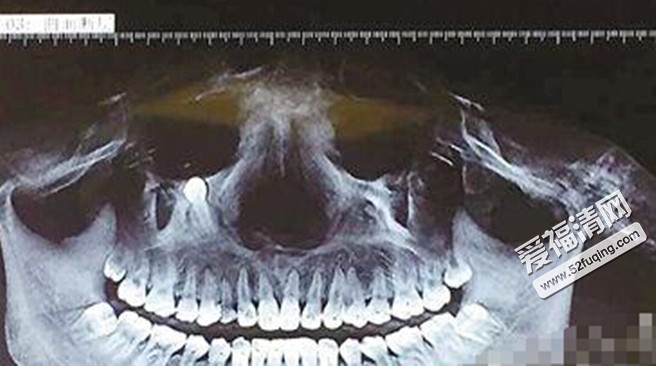

你能想象眼睛附近长有牙齿的事情吗?听起来比较诡异,牙齿怎么会与眼睛有关系,根本是风马牛不相关的两个物体。不过这事却真实的发生在四川广安28岁女子曹某身上。接下来就来看一下具体情况。

前不久,曹某在广州打工的时候,突然发现自己吃食物比较吃力,连苹果都咬不动了。于是赶紧到医院检查,检查结果让她吓了一跳,右眼眶下有一颗锥形牙齿。